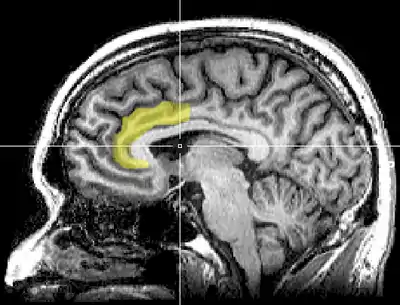

Cognitive dissonance produces a state of negative affect, which motivates the person to reconsider the causative behavior in order to resolve the psychological inconsistency that caused the mental stress.[100][101][102][103][104][105] As the affected person works towards a behavioral commitment, the motivational process then is activated in the left frontal cortex of the brain.[100][101][102][106][104]

The study Neural Activity Predicts Attitude Change in Cognitive Dissonance[108] (Van Veen, Krug, etc., 2009) identified the neural bases of cognitive dissonance with functional magnetic resonance imaging (fMRI); the neural scans of the participants replicated the basic findings of the induced-compliance paradigm. When in the fMRI scanner, some of the study participants argued that the uncomfortable, mechanical environment of the MRI machine nevertheless was a pleasant experience for them; some participants, from an experimental group, said they enjoyed the mechanical environment of the fMRI scanner more than did the control-group participants (paid actors) who argued about the uncomfortable experimental environment.[108]

The results of the neural scan experiment support the original theory of Cognitive Dissonance proposed by Festinger in 1957; and also support the psychological conflict theory, whereby the anterior cingulate functions, in counter-attitudinal response, to activate the dorsal anterior cingulate cortex and the anterior insular cortex; the degree of activation of said regions of the brain is predicted by the degree of change in the psychological attitude of the person.[108]

The Neural Basis of Rationalization: Cognitive Dissonance Reduction During Decision-making[35] (Jarcho, Berkman, Lieberman, 2010) applied the free-choice paradigm to fMRI examination of the brain's decision-making process whilst the study participant actively tried to reduce cognitive dissonance. The results indicated that the active reduction of psychological dissonance increased neural activity in the right-inferior frontal gyrus, in the medial fronto-parietal region, and in the ventral striatum, and that neural activity decreased in the anterior insula.[35] That the neural activities of rationalization occur in seconds, without conscious deliberation on the part of the person; and that the brain engages in emotional responses whilst effecting decisions.[35]

Emotional correlations

The results reported in Contributions from Research on Anger and Cognitive Dissonance to Understanding the Motivational Functions of Asymmetrical Frontal Brain Activity[111] (Harmon-Jones, 2004) indicate that the occurrence of cognitive dissonance is associated with neural activity in the left frontal cortex, a brain structure also associated with the emotion of anger; moreover, functionally, anger motivates neural activity in the left frontal cortex.[101][20] Applying a directional model of Approach motivation, the study Anger and the Behavioural Approach System (2003) indicated that the relationship between cognitive dissonance and anger is supported by neural activity in the left frontal cortex that occurs when a person takes control of the social situation causing the cognitive dissonance. Conversely, if the person cannot control or cannot change the psychologically stressful stimulation, they are without a motivation to change the circumstance, then there arise other, negative emotions to manage the cognitive dissonance, such as socially inappropriate behavior.[101][112][111]

The anterior cingulate cortex activity increases when errors occur and are being monitored as well as having behavioral conflicts with the self-concept as a form of higher-level thinking.[113] A study was done to test the prediction that the left frontal cortex would have increased activity. University students had to write a paper depending on if they were assigned to a high-choice or low-choice condition. The low-choice condition required students to write about supporting a 10% increase in tuition at their university. The point of this condition was to see how significant the counter-choice may affect a person's ability to cope. The high-choice condition asked students to write in favor of tuition increase as if it were their completely voluntary choice. The researchers use EEG to analyze students before they wrote the essay, as dissonance is at its highest during this time (Beauvois and Joule, 1996). High-choice condition participants showed a higher level of the left frontal cortex than the low-choice participants. Results show that the initial experience of dissonance can be apparent in the anterior cingulate cortex, then the left frontal cortex is activated, which also activates the approach motivational system to reduce anger.[113][114]